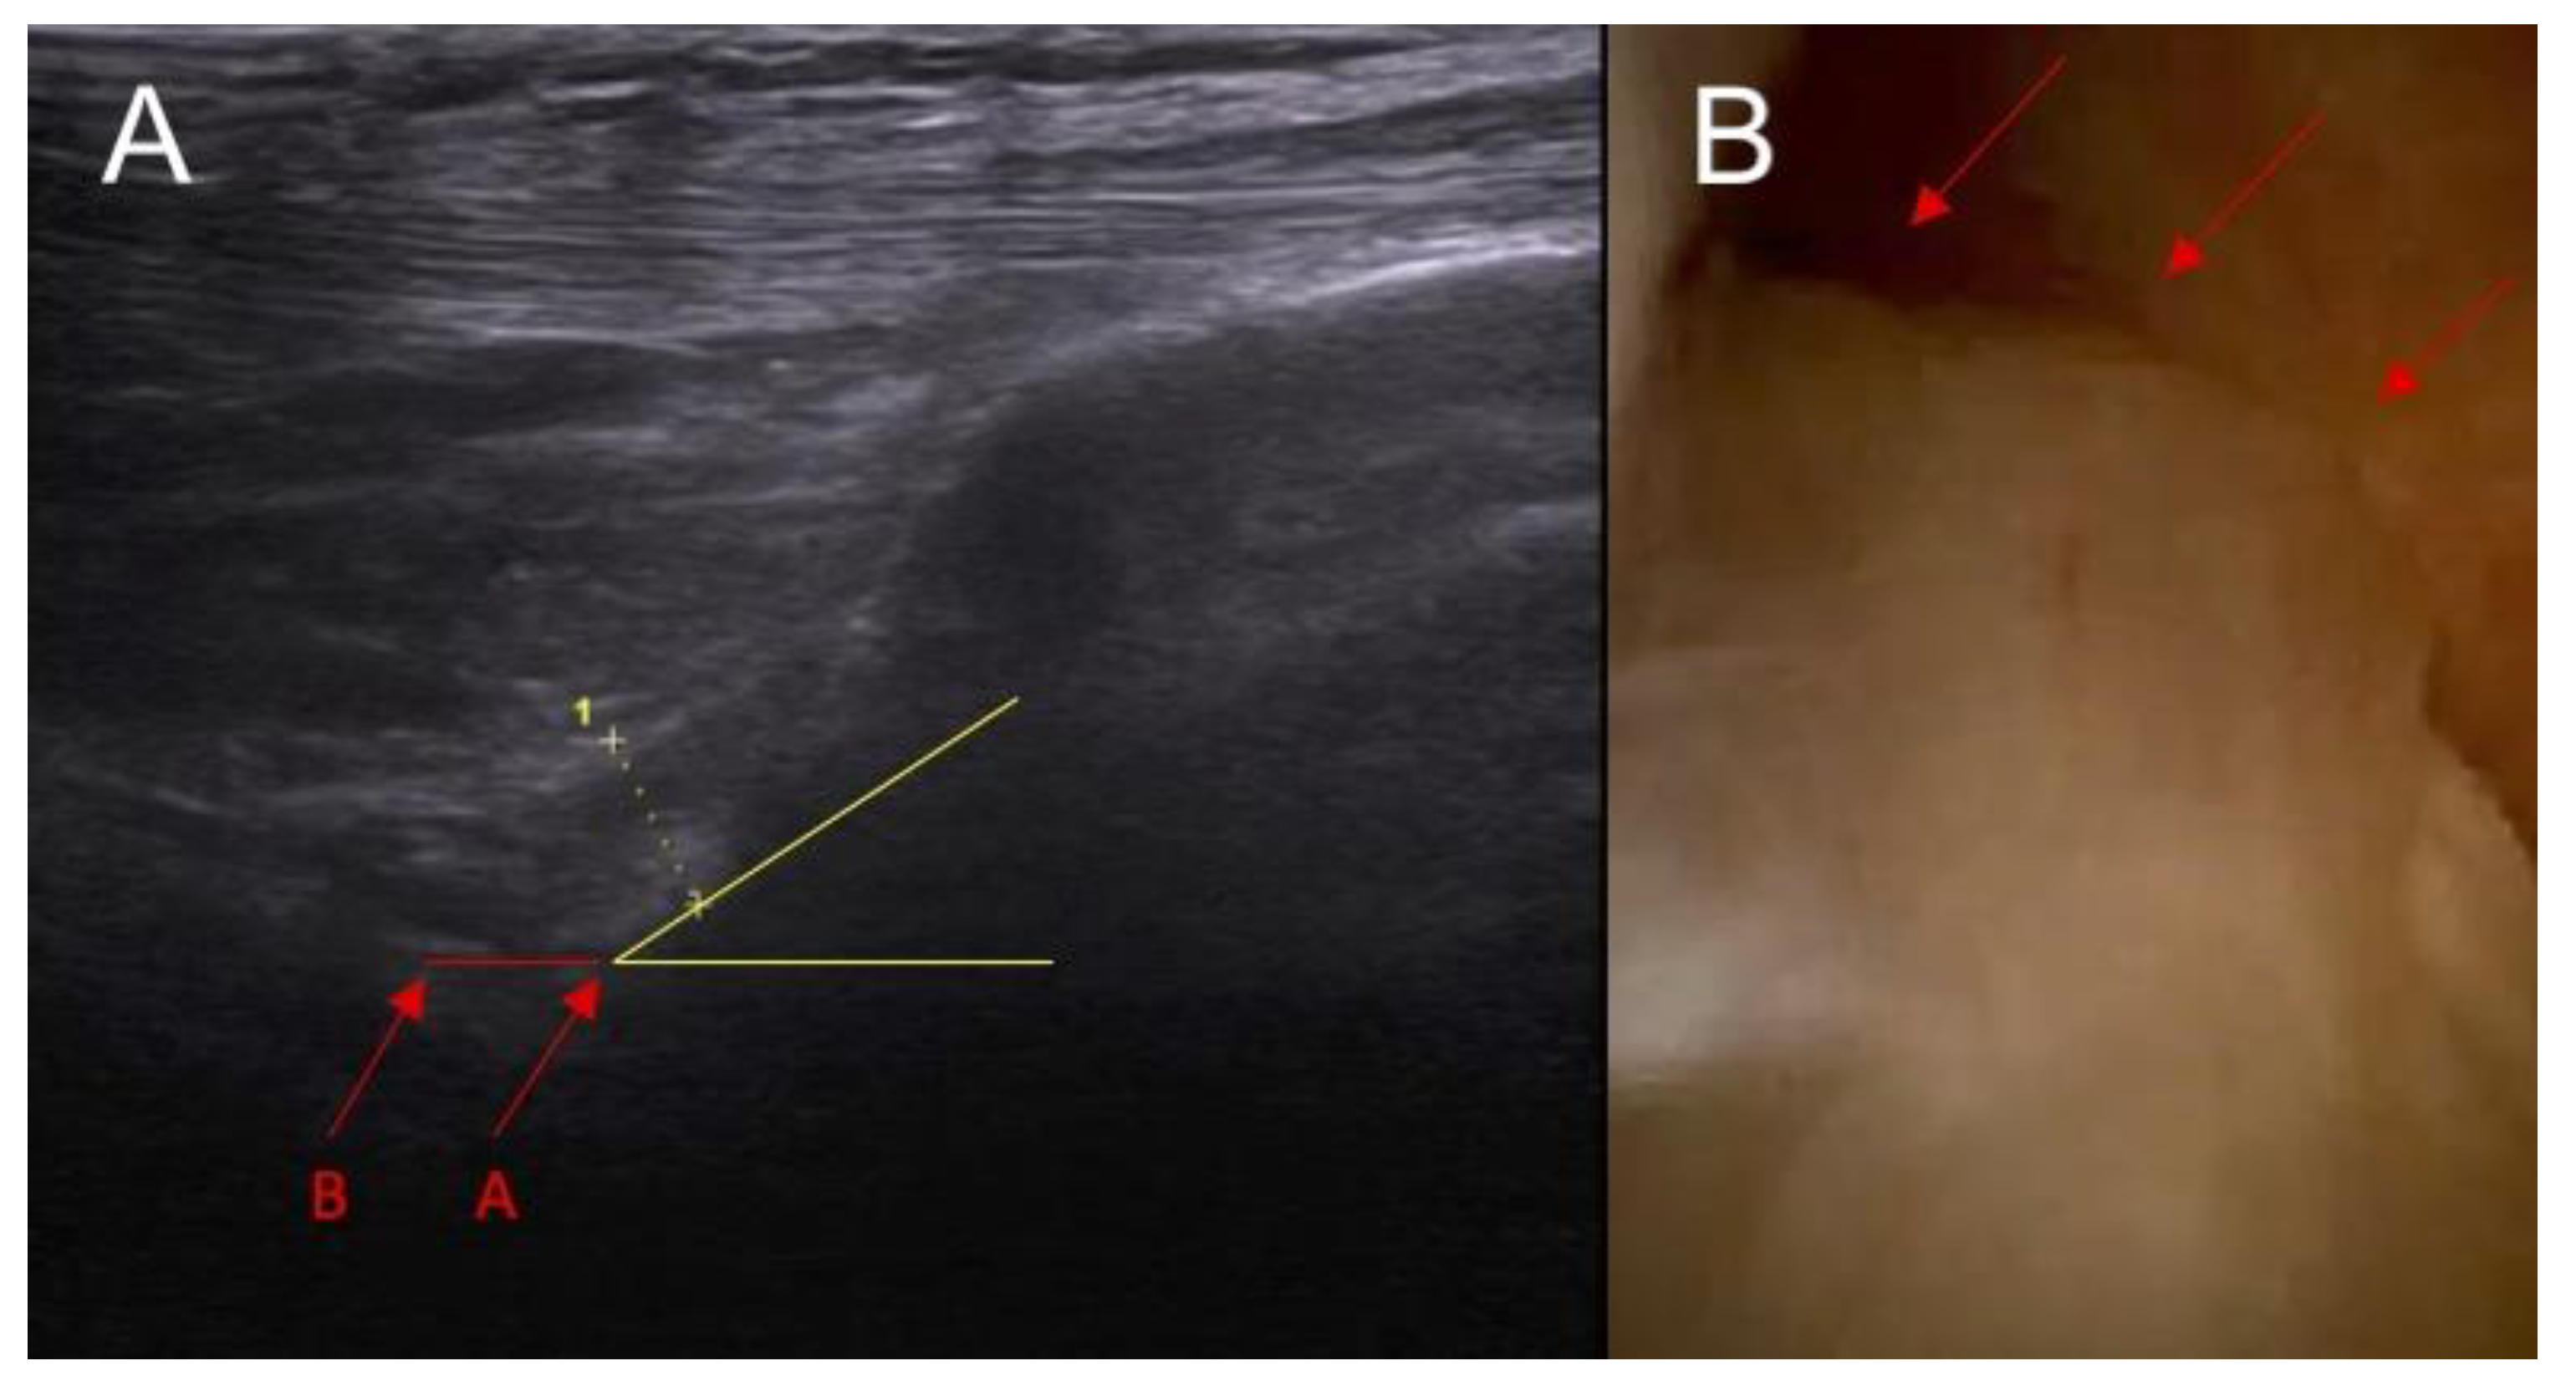

Figure 1.

Anatomical part of the study. (A) Ultrasound examination: point A—baseline point of the ACL in the ultrasound image before the application of force and point B—the same point after the application of force in the anterior drawer test. Section A–B—actual functional instability on ultrasound examination. Yellow lines indicate the inclination of ACL. (B) arthroscopy view— arrows indicate intersection of the ACL.